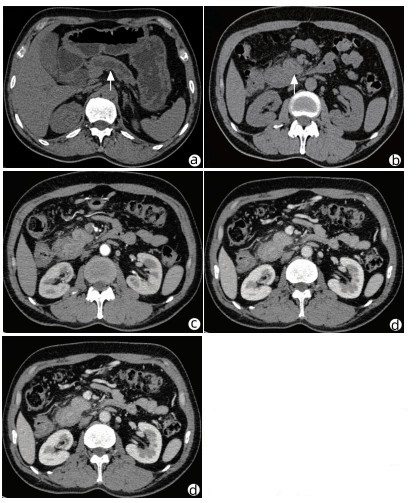

Acute pancreatitis caused by a hematoma in the duodenal wall: A case report

Mengran ZHU, Shanshan JIANG, Tingting YU, Yun BAI, Dingxin WANG, Linping SHI

2022, 38(3): 639-642. DOI: 10.3969/j.issn.1001-5256.2022.03.029

Abstract(1282) HTML (240) PDF (3475KB)(41)

Abstract: